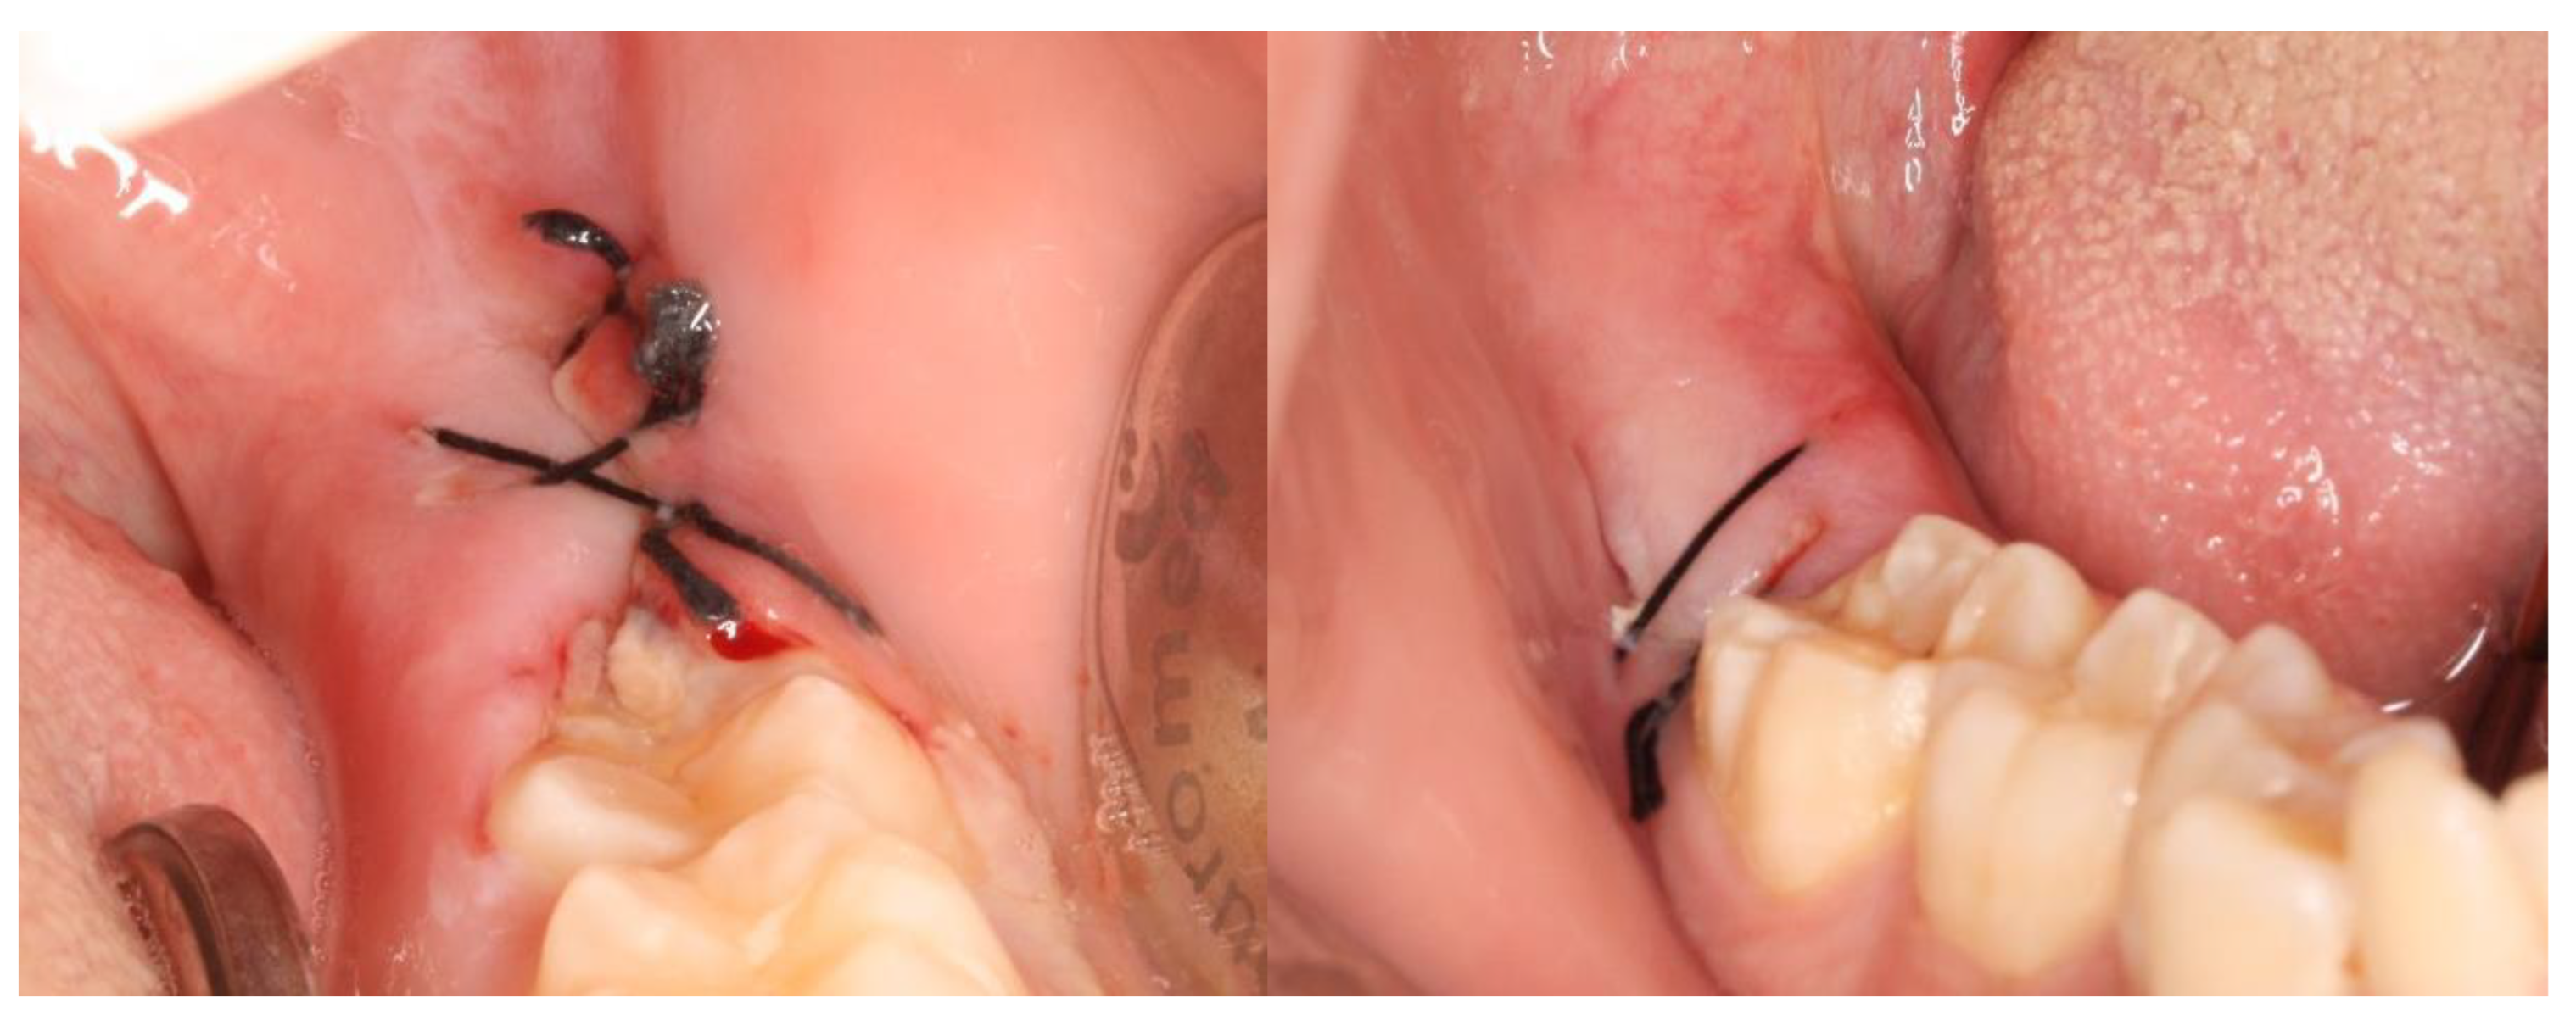

2. Materials and Methods

2.2. Definition of the Variables in Study and Follow-Up of Patients

3. Results